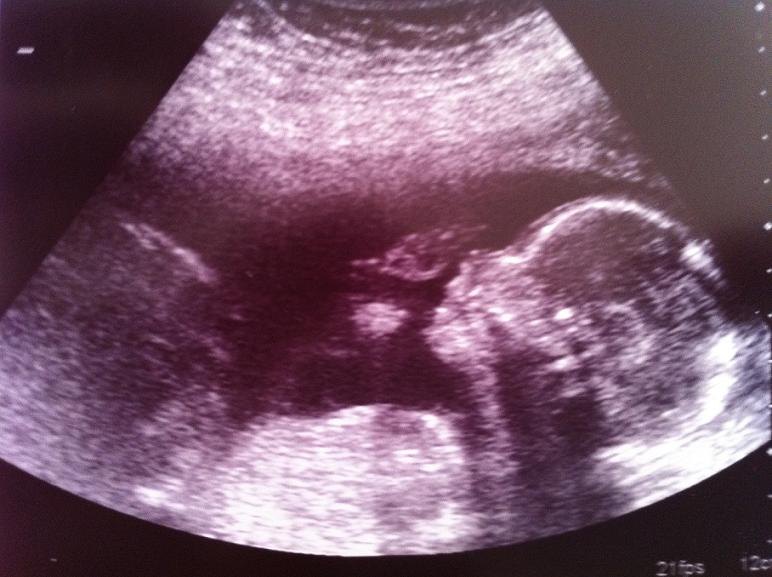

Nå men hun roder rundt og siger: "Ja, jeg er ret sikker på at det er en lille pige..." (10 sekunder går) "Nej vent... Et lårben, to lårben og noget imellem. Det er sgu en dreng. I skal have en dreng."

Og rigtig nok... lige der midt imellem benene kunne man se en tap og en pung. Og lige til venstre kunne man se min kæreste storjuble!

Og hun var ret imponeret over at hans lårbensknogle var 3 cm (Er der andre der kender det mål på jeres) Men håber i hvert fald at han arver sin fars laaange ben, da babys mor har sat røv ALT for tidligt!